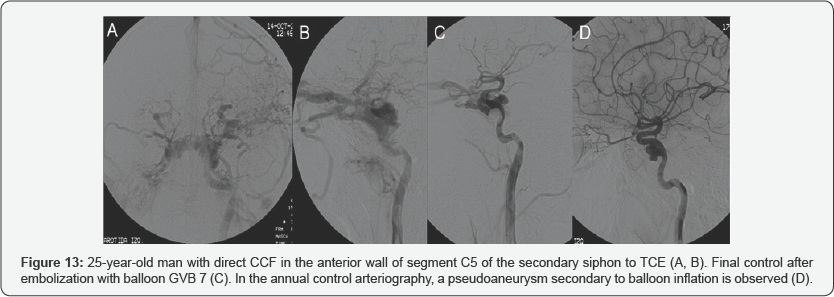

As late complications, it is worth mentioning a patient with persistent CCF after embolization with coils, with a decrease in flow and improvement of ocular symptoms, and another patient with a pseudoaneurysm after balloon embolization, which decreased in arteriography of control performed 12 and 24 months later (Figure 13).